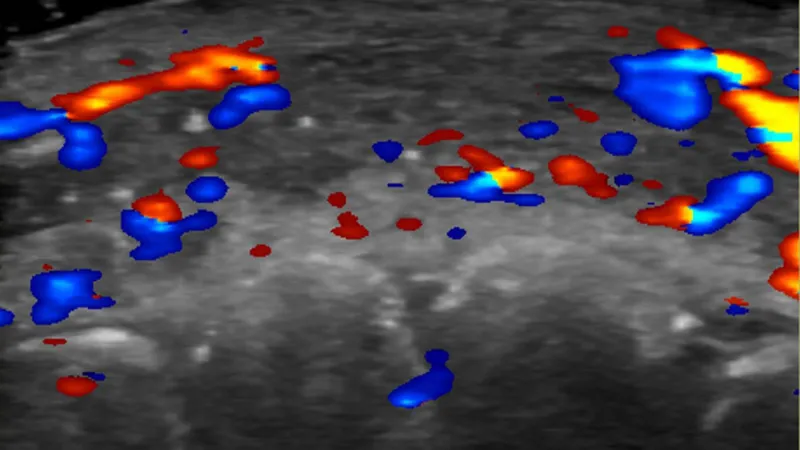

برازیل کی یونیورسٹی آف ساؤ پالو کی ڈاکٹر روزا سگرسٹ کی قیادت میں محققین نے 100 فلر انجیکشن کے کیسز کا الٹراساؤنڈ کے ذریعے مطالعہ کیا جہاں فلرز کے استعمال سے پیچیدگیاں پیدا ہوئی تھیں۔

نتائج کے مطابق تقریباً نصف کیسز میں چہرے کی سطحی اور گہری شریانوں کو جوڑنے والی چھوٹی خون کی نالیوں میں خون کا بہاؤ نہیں تھا۔

علاوہ ازیں ایک تہائی کیسز میں اہم شریانوں میں خون کی روانی غائب تھی۔

ڈاکٹر سگرسٹ کا کہنا ہے کہ فلرز دینے سے پہلے الٹراساؤنڈ کے ذریعے خون کی نالیوں کی شناخت ضروری ہے۔

پیچیدگی کی صورت میں الٹراساؤنڈ کی مدد سے صحیح مقام پر علاج کیا جا سکتا ہے۔

غیر ہدایت شدہ انجیکشنز کی بجائے الٹراساؤنڈ سے رہنمائی حاصل کرنے پر کم دوائی استعمال کر کے بہتر نتائج حاصل کیے جا سکتے ہیں۔